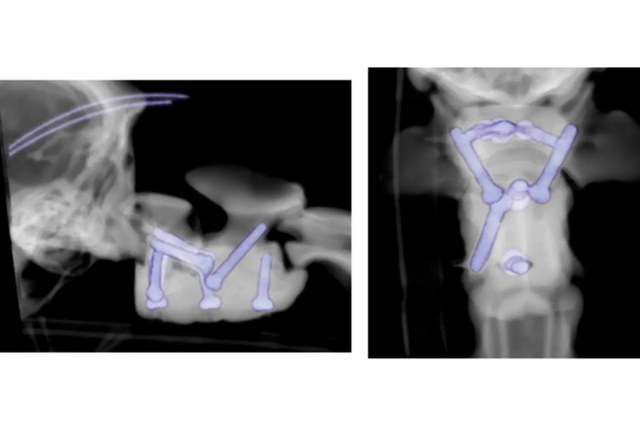

아서의 보호자 '나탈리 존스(Natalie Jones)'는 급히 영국  체셔 주에 위치한 체스터게이츠 동물병원으로 반려견을 데려갔다. 그곳에서 반려견 아서는 엑스레이, MRI를 촬영하는 등 종합 검진을 받았다. 진료 결과 반려견의 척추 일부가 제대로 연결되지 않아 척수를 압박하고 있고, 사지 기능까지 상실되고 있음을 발견했다.

이에 아서는 4시간 동안 수술을 받았으며, 담당 의사는 3D 프린터를 이용해 맞춤형 척추 나사와 수술용 시멘트를 척추에 삽입했다. 수의사 로시오 올란디(Rocio Orlandi)는 수술 전 아서의 상태가 '매우 심각했다'고 말했다. 로시오 올란디는 "이상 부위가 뇌에서 척수로 이어지는 부위인 뇌간과 가까워 생명을 위협할 수 있어 심각했다"라고 전했다.

이어 로시오 올란디는 "3D 프린팅 기술을 사용했기 때문에 복잡한 수술의 정확성이 향상돼 성공적인 결과를 얻었다"라고 말했다. 수술한지 3개월이 지난 지금 아서는 어떻게 지내고 있을까. 아서는 새로운 척추 뼈가 생겼고, 천천히 걷기 시작했다고 한다.